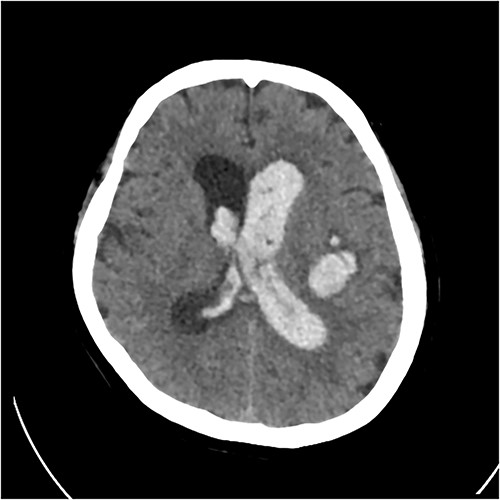

A 67 year-old woman was admitted to our service from the neurosurgical department for rehabilitation after a spontaneous left basal ganglia haemorrhage and diffuse intraventricular haemorrhage with hydrocephalus. She had been initially found unresponsive at home with coffee ground vomitus and incontinence of urine. An urgent computed tomography (CT) scan of the brain showed a large intracranial haemorrhage with intraventricular bleeding and hydrocephalus (Fig. 1). Her acute admission involved an extraventricular drain inserted by the neurosurgery service. A repeat CT brain performed 10 days later showed stable multicompartmental haemorrhage, and the extraventricular drain was removed. A ventriculoperitoneal shunt was inserted on Day 27 for ongoing management of the hydrocephalus. A digital subtraction angiogram showed no underlying aneurysm or arteriovenous shunt.

Initial CT revealing acute left-sided intraparenchymal haemorrhage with intraventricular extension and mass effect.